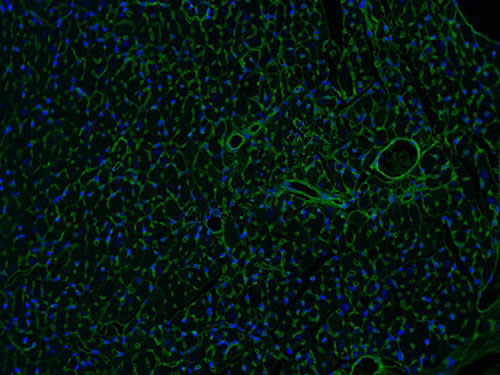

實(shí)驗(yàn)結(jié)果展示:

WGA染色-小鼠心臟

麥胚凝集素(WGA)是從谷物中提取出來,可以特異性的結(jié)合心肌細(xì)胞膜上的一種糖蛋白,二者結(jié)合起來可以將心肌細(xì)胞膜染出來。WGA可以把心肌細(xì)胞膜染出來,這樣是否肥大的細(xì)胞從圖像與正常組的對(duì)比就可以看出,也可以用專門的軟件對(duì)染出的細(xì)胞進(jìn)行直徑、面積等的測(cè)量,能夠分析心肌細(xì)胞是否肥大。